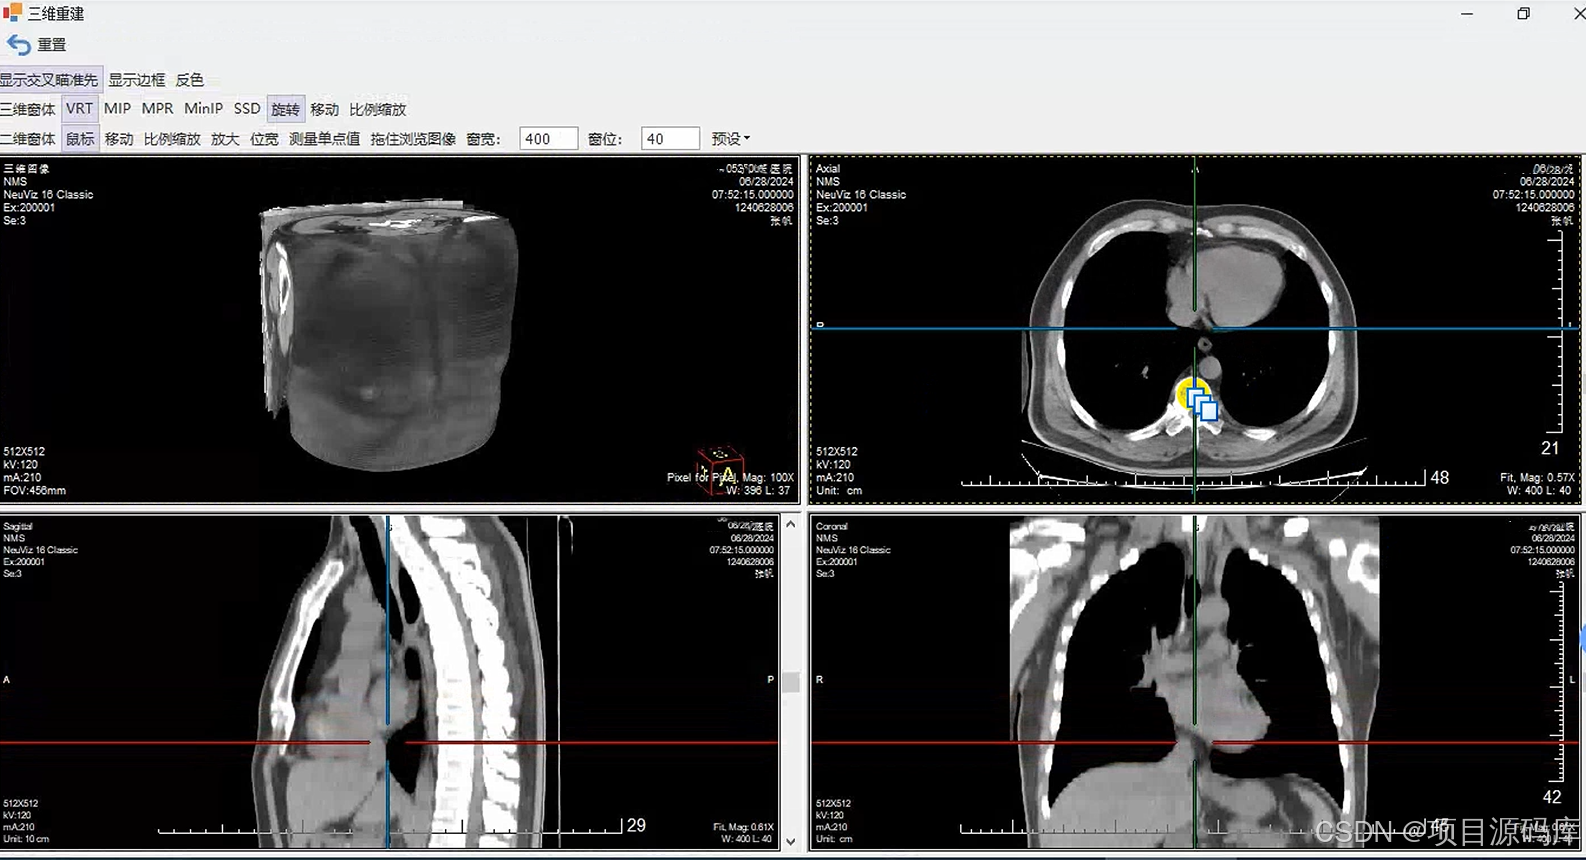

三维重建后处理

CT三维重建技术是指经过计算机软件处理,将连续横断层扫描所收集的信息重建为直观的三维立体图像的一种影像学技术,是图像处理技术的一次重大飞跃。更便于医生诊断病灶。

CT三维重建主要有六种基本后处理方法

多层面重建(MPR)

最大密度投影(MIP)

表面阴影遮盖(SSD)

容积漫游技术(VRT)

多层面重建(MPR):MPR适用于任一平面的结构成像,以任意角度观察正常组织器官或病变,可以显示腔性结构的横截面以观察腔隙的狭窄程度、评价血管受侵情况、真实地反映器官间的位置关系等。

最大密度投影(MIP):最大密度投影是将一定厚度(即CT层厚)中最大CT值的体素投影到背景平面上,以显示所有或部分的强化密度高的血管和/或器官。

最小密度投影(minlP):和MIP正好相反,反映的是一定层厚图像中CT值最低的体素,所以常用来显示胆道、气道等组织结构。

曲面重建技术(CPR):这种重建技术是在一个维度上选择特定的曲线路径,将该路径上得所有体素在同一平面上进行显示,可以一次评价曲度较大的结构如脾动脉、胰管、冠状动脉等管状结构的全长情况。

容积漫游技术(VRT):可以对动静脉血管、软组织及骨结构等进行立体塑形成像,也可以显示支气管树、结肠及内耳等结构,三维成像功能非常强大,形态及色彩逼真对于复杂结构的成像有一定优势。

表面阴影遮盖(SSD):表面阴影遮盖是将操作者的眼睛作为假设光源方向,投射到CT值在设定阈值以上的体素上则不再透过继续成像,仅呈现所有表面体素的集合立体图形,适用于显示CT值与其他结构相差较大的组织结构成像,通俗来说,SSD图像就像是黑白的塑形图像,所以临床上主要用于显示骨骼病变或是结肠CT重建。

PACS系统支持3D阅片的原理

PACS系统支持3D阅片的原理基于从一系列二维医学影像(如CT或MRI扫描的切片)中重建三维模型的技术。以下是实现这一功能的关键步骤和技术要点:

数据获取:首先,从PACS系统中导出原始的二维医学影像数据,这些数据通常是DICOM格式,包含了详细的患者信息和图像数据。

图像预处理:对原始图像进行噪声过滤、对比度增强等处理,以提高重建质量。这一步骤是确保后续三维重建准确性的基础。

图像配准:由于不同时间或角度获取的图像可能有微小的位移,需要通过配准算法将这些图像精确对齐,确保重建的三维模型连续且一致。

后处理与分析:重建后的3D模型可以进一步进行旋转、缩放、切割等操作,以不同视角观察,辅助医生进行更深入的分析和诊断。

可视化与交互:通过高性能图形处理器(GPU),PACS系统能够实时渲染3D图像,医生可以通过鼠标或触摸屏进行交互,动态调整视图,从而获得更直观的解剖结构理解。

通过这些技术,PACS系统不仅存储和管理二维医学影像,还能提供强大的3D阅片功能,帮助医生进行更精确的诊断和治疗规划。